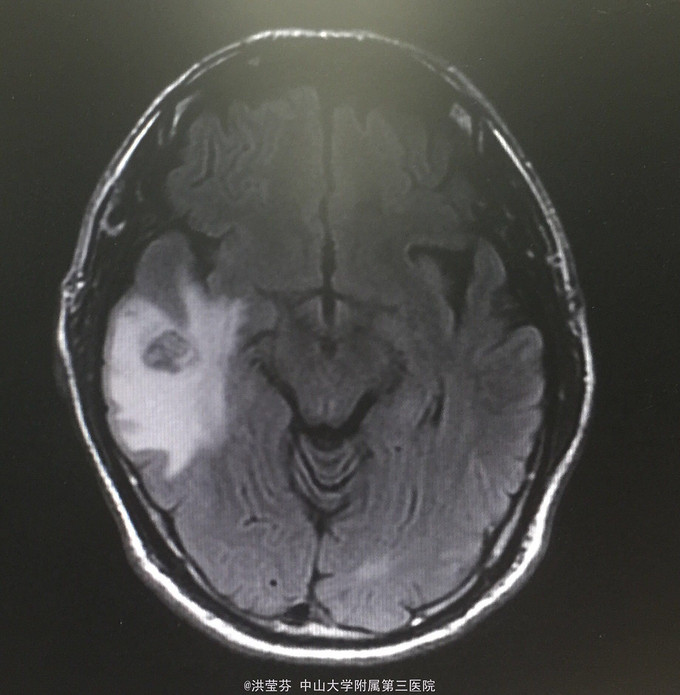

查体:KPS 60分,BSA 1.83m2,T 38.5℃,全身浅表淋巴结未触及明显肿大,胸壁可见浅表静脉曲张,呼吸急促,左下肺、右中下肺呼吸音明显减弱,其余肺野呼吸音促,可闻及少许实性啰音,心率110bpm,律齐,腹软,全腹无压痛、反跳痛,未扪及明显包块,肝脾肋下未触及,移动性浊音(——),肠鸣音正常,4次/分,双下肢无凹陷性水肿。 辅助检查:血常规无特殊,生化转氨酶稍升高,低钠低氯,CRP 227.9mg/L,凝血四项:Fib 8.14g/L。复查胸部CT提示:1.胸腺癌并纵膈淋巴结及双肺多发转移瘤,右心房、上腔静脉受侵并癌栓形成,病变较前进展。2.双肺炎症,以右肺为著。3.双侧胸腔及心包积液。上腹部CT提示:1.下腔静脉早显并肝表面多发侧支形成,考虑右心流出道阻塞所致;腹壁静脉曲张。头颅MR提示右侧颞叶强化灶,结合病史,考虑转移瘤,伴瘤灶少量出血可能,瘤周脑水肿。